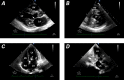

Hepatocellular Carcinoma Involving the Left Ventricle